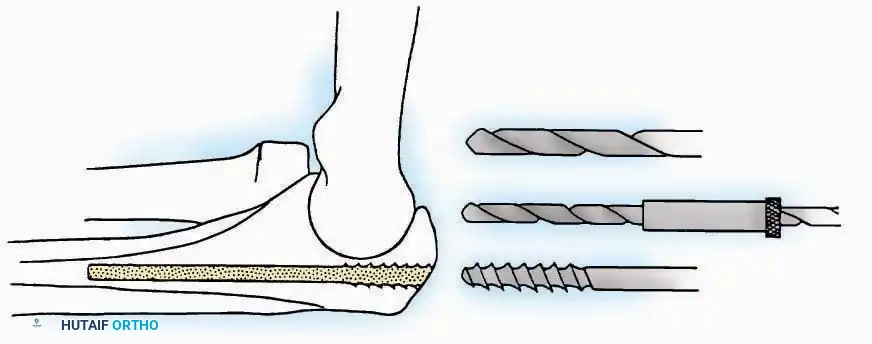

SURGICAL APPROACHES TO THE CALCANEUS

Lateral Approach (Extensile Lateral)

This is the workhorse approach for open reduction and internal fixation (ORIF) of displaced intra-articular calcaneal fractures.

Indications: ORIF of calcaneus fractures, lateral wall exostectomy, subtalar arthrodesis.

Positioning: Lateral decubitus with the operative leg up, or supine with a large bump under the ipsilateral hip to internally rotate the leg.

Surgical Technique:

* Incision: Begin the incision on the lateral margin of the Achilles tendon near its insertion. Extend it distally to a point 4 cm inferior and 2.5 cm anterior to the lateral malleolus. (For trauma, a classic L-shaped extensile incision is often used, dropping straight down anterior to the Achilles, then curving gently toward the base of the 5th metatarsal).

* Superficial Dissection: Divide the superficial and deep fasciae. It is imperative to create a "full-thickness" flap containing skin, subcutaneous fat, and periosteum to prevent flap necrosis.

* Nerve Protection: The sural nerve crosses the proximal and distal limbs of this approach. It must be identified and protected within the anterior flap.

* Deep Dissection: Isolate the peroneal tendons (longus and brevis). Incise and elevate the periosteum below the tendons to expose the lateral wall of the calcaneus.

* Tendon Management: If severe deformity or infection is present, the peroneal tendons may be divided via Z-plasty and repaired at the conclusion of the case, though this is rarely necessary in modern fracture care.